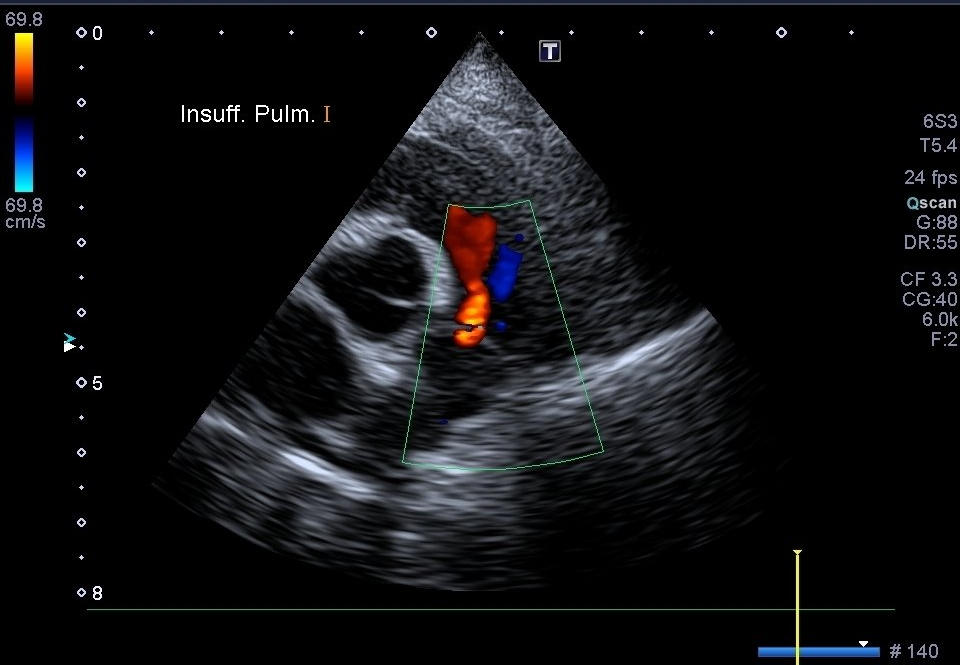

Échographie Cardiaque

Les échographies thoraciques permettent quand à elle d’étudier et de suivre l’évolution des pathologies cardiaques mais également d’observer des épanchements ou des tumeurs thoraciques.